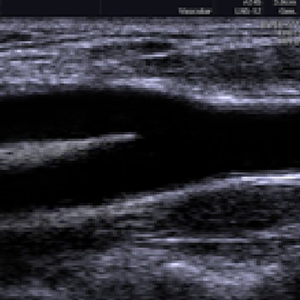

Examines the vessels that supply the brain with oxygen and their back-up arteries. Documents and measures plaque build-up. There is NO treatment for a completely blocked carotid artery.